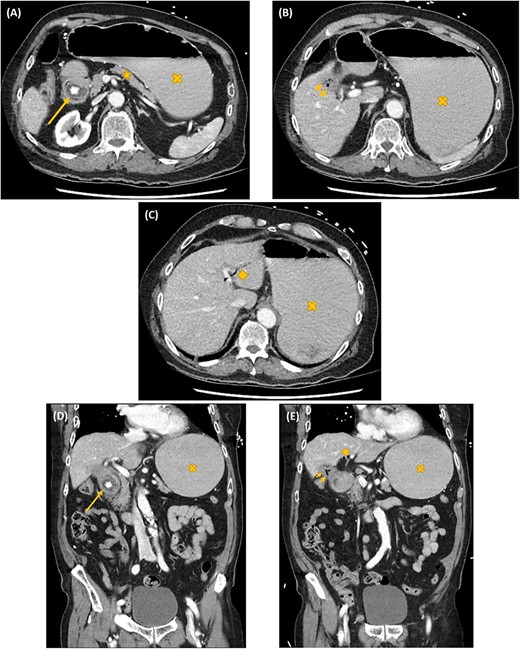

Axial (A–C) and coronal (D, E) computed tomography images showing gastric outlet obstruction (cross) due to a 3 cm hyperdense ectopic gallstone between the first and second parts of duodenum (arrow), with intrahepatic pneumobilia (diamond) and a decompressed gallbladder (arrow heads). This Rigler’s triad of findings was consistent with a cholecystoduodenal fistula and Bouveret syndrome.

On investigation, an acute inflammatory response, an acute kidney injury and a marked metabolic alkalosis were evident on biochemistry, but there was no cholestasis or hepatic dysfunction. Subsequent abdominal computed tomography (CT) identified a 3 cm hyperdense ectopic gallstone that was impacted between the first and second parts of the duodenum. There was gastric outlet obstruction proximal to this gallstone. A cholecystoduodenal fistula was noted with the presence of intrahepatic pneumobilia. These findings are collectively known as the Rigler’s triad (Fig. 1). Following initial resuscitative measures, an emergency laparotomy was undertaken. The operation was 3 h in duration and consisted of extensive adhesiolysis, duodenorrhaphy following stone extraction, subtotal cholecystectomy and finally an omental patch of the cholecystoduodenal fistula. On post-operative Day 6, his recovery was complicated with bilateral pulmonary emboli leading to both respiratory failure and obstructive shock. Despite thrombolysis and resuscitation, he succumbed 10 h later.

The Rigler’s triad of gastric outlet obstruction, ectopic gallstone and pneumobilia on radiological imaging is pathognomonic for Bouveret syndrome [5, 7, 11]. This diagnosis can be established on CT, magnetic resonance cholangiopancreato-graphy (MRCP), ultrasound or upper gastrointestinal (UGI) endoscopy. CT is usually the most practical—its sensitivity for Rigler’s triad is between 75 and 78% [4, 11, 12]. One of the main limitations is its inability in visualizing isodense gallstones. One study reported that pneumobilia was evident in 60%; ectopic gallstone in 50%; and gastric outlet obstruction in 33% of cases with Bouveret syndrome on CT [13]. MRCP provides substantially improved diagnostic details on fistulous tracts, but its diagnostic potential is often limited by its accessibility in many clinical institutions. Ultrasound is useful for identifying gallstones and pneumobilia. Nevertheless, its sensitivity for Rigler’s triad is only 11%—intestinal distension and gas can make ultrasonography technically challenging [12]. It can also be tricky to localize the gallstone (orthotopic versus ectopic) with a collapsed gallbladder [12]. UGI endoscopy has the potential dual benefit of diagnosing and decompressing gastroduodenal distension simultaneously. However, the ectopic enteric gallstone and the enteric fistulous opening are visualized only in 69 and 31% of cases, respectively [5, 12, 13]. The success rate of endoscopic retrieval of the ectopic enteric gallstone is only about 10% [13].